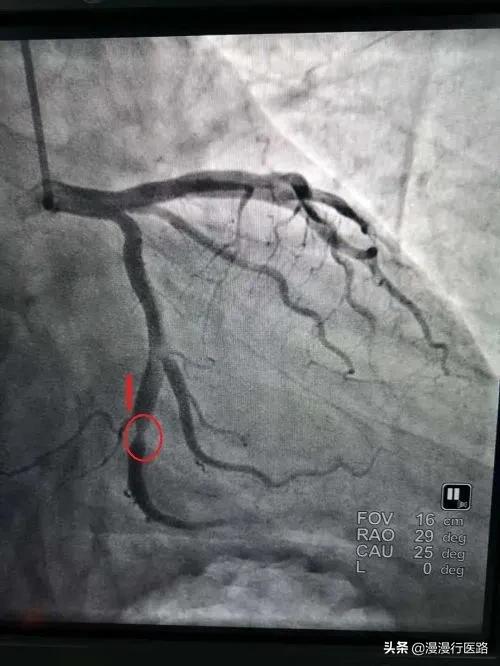

再三の説得の結果、ラオフーは入院することになり、私はラオフーに心電図検査を受けるよう手配した。その結果、左側の血管が99%狭くなっており、適時発見したおかげですぐにふさがることがわかった。しかし、国内のステントは7,500円、その他の手術器具も数万円する。老福のような家族にとって、これは実に重荷であった。 たまたま、王医師がステント留置のプロセスに関する臨床研究という実験の責任者であったので、彼は老福に、この研究に参加する意思があるかどうか、無料でステントを留置することができるかどうかを告げた。ラオフーは快く承諾した。何しろ1万元近く節約できるのだから。ラオフーを病室に送り返すとき、ラオフーはまだ心配そうに、どうしたのかと彼に尋ねた。

その後、関連する検査を手配し、画像診断の結果、左冠動脈の狭窄が85%に達しており、ステント留置が必要であることがわかった。

張さん、あなたの左冠動脈の狭窄の程度は85%に達しており、最後の比較は明らかに深刻です。